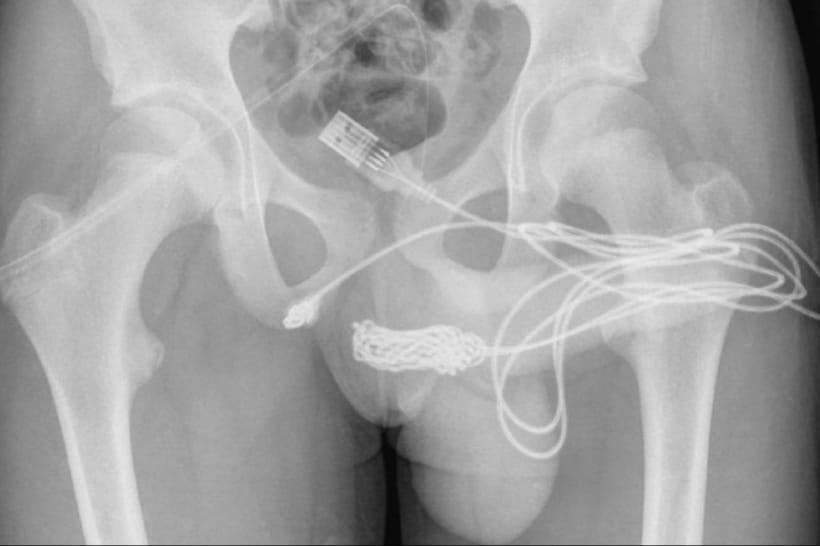

Фахівець відправив підлітка зробити рентген. На знімку він побачив, що кабель зав'язався всередині пацієнта на величезний вузол. Тоді було вирішено робити операцію. Лікарі зробили невеликий надріз між анусом та геніталіями і витягнули сторонній предмет.